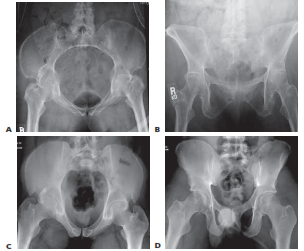

Radiographic evaluation forms the cornerstone of preoperative planning. The standard trauma series includes an anteroposterior (AP) view of the pelvis, supplemented by inlet and outlet views to assess the true rotational and vertical displacement of the pelvic ring. Judet views may be added if concomitant acetabular fractures are suspected.

Image